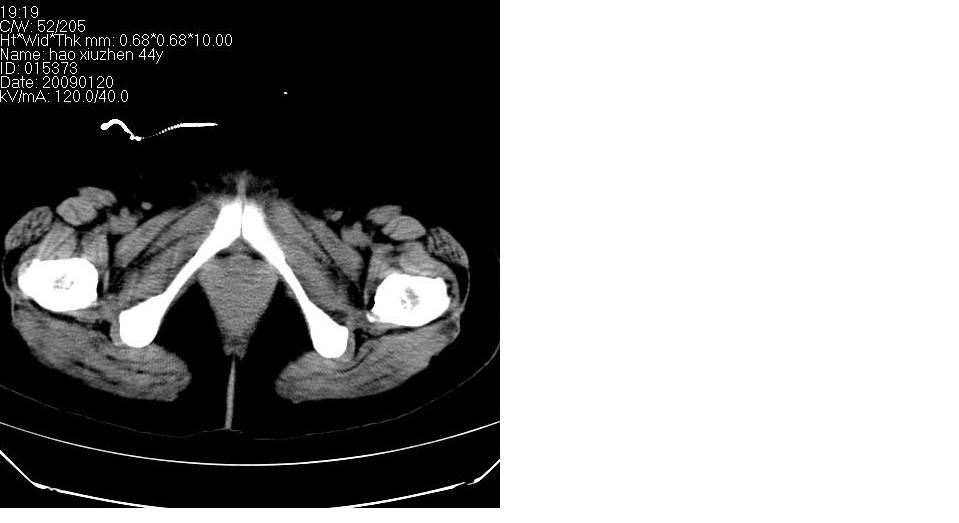

标题: CT17773B盆腔CT平扫

女 44岁,于ct17773号病例同一个病人。有结果我会尽快告诉大家。

盆腔及腹腔积液,原因待查。